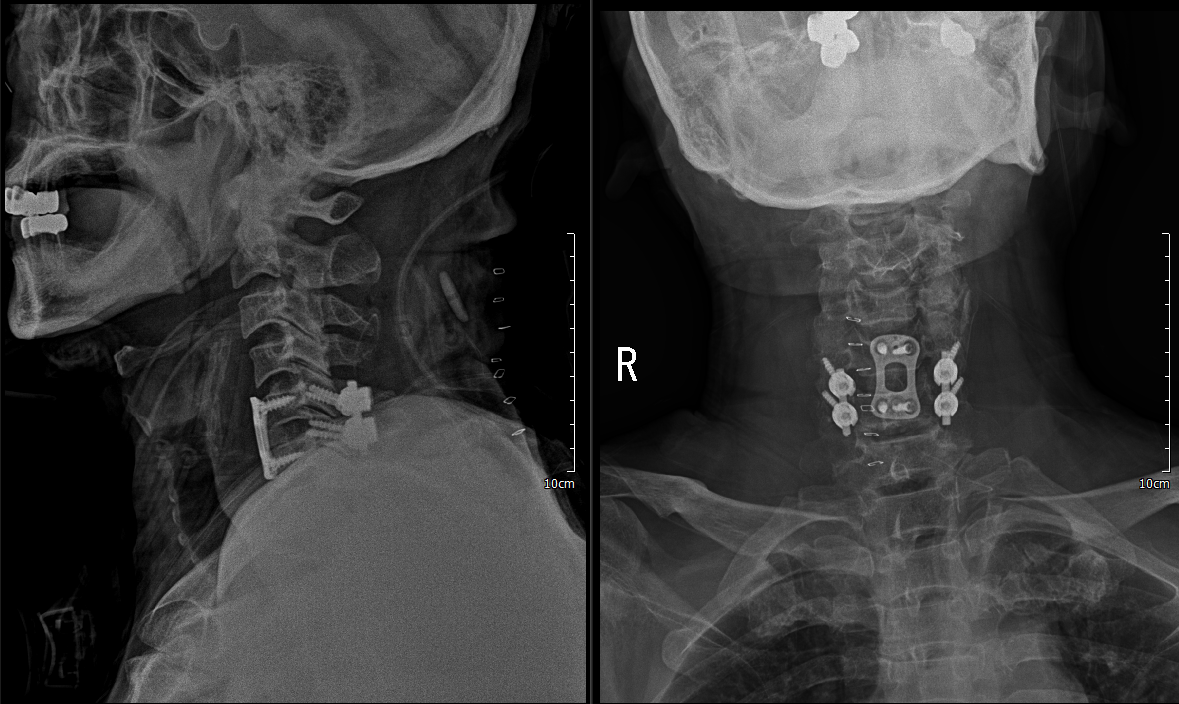

x ray 측면에서 보면 경추 5/6 후관절 탈골이 확인이 됨.

reduction 된 것을 확인 하였음.

1. C5/6 ACDF & iliac bone graft(Rt)

2. PF C5/6

C5/6 ACDF & iliac bone graft(Rt)

하지만 안정성 확보를 위해 5일 후 뒤쪽으로 고정술 시행

lateral mass screw을 사용하여 고정술 시행